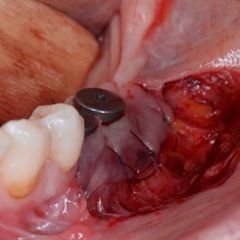

Augmentation in the third quadrant with allogeneic bone plates and autologous bone chips using the shell technique: initial situation after opening (Fig. 7), buccal and lingual fixation (Fig. 8), filling of the bone bed (Fig. 9)

The augmentation then took place in the third quadrant. To this end, two allogeneic bone plates (maxgraft® cortico, Straumann GmbH, Freiburg, Germany) were first opened and immersed in sterile saline solution for 10 minutes. During this time the flap was prepared in regions 35-37. The allogeneic bone plates were divided according to the anatomical situation and fixed buccally and lingually in the fourth quadrant using 4 micro-screws. The resulting cavity was then filled with autogenous bone chips that were left over from the augmentation in the third quadrant.